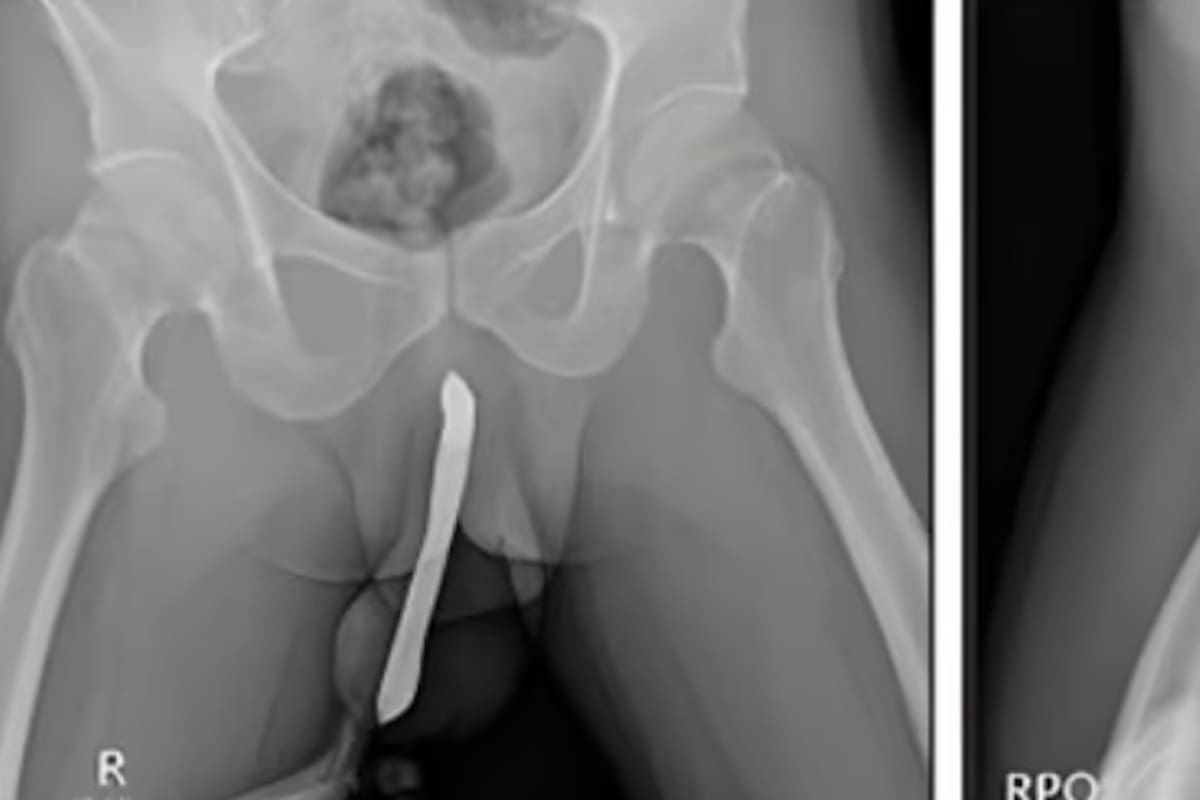

Indonesia.- Un hombre de 43 años en Indonesia sufrió una fractura de pene después de que un cepillo de dientes, que había introducido en su pene como parte de una cirugía casera para su “satisfacción sexual”, se rompiera durante las relaciones sexuales.

El paciente esperó 12 horas antes de buscar atención médica por el dolor insoportable. Los médicos del Hospital Académico General Soetomo en Java Oriental realizaron una operación de dos horas para reparar su pene fracturado, que presentaba una “deformidad en berenjena”, un signo revelador de fractura de pene.